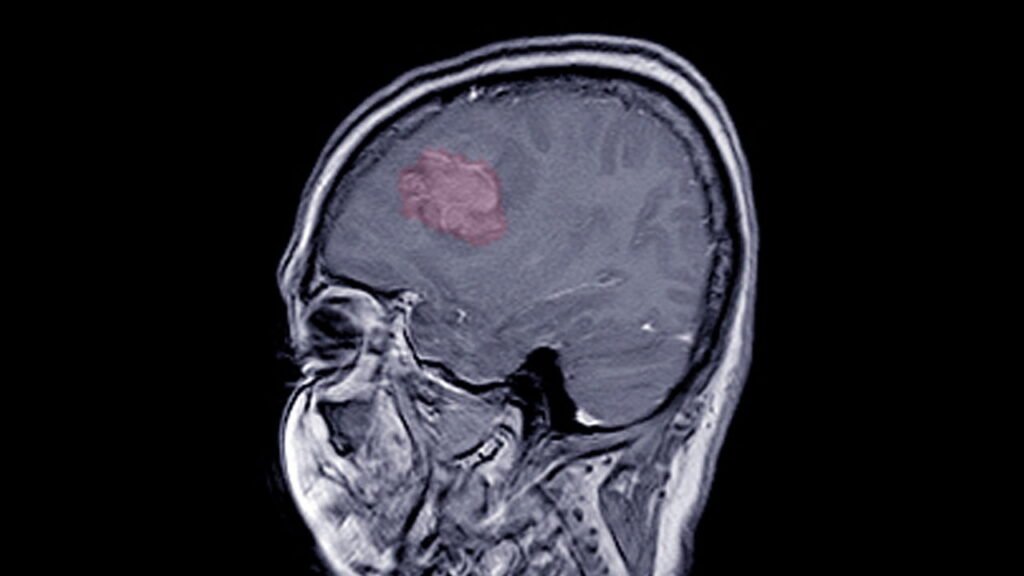

Os Tumores Cerebrais representam uma das condições neurológicas mais desafiadoras da medicina moderna. Eles surgem a partir da multiplicação anormal de células dentro do cérebro e podem provocar complicações sérias por compressão de estruturas vizinhas e pelo aumento da pressão intracraniana.

Esses sintomas, isolados ou combinados, devem ser sempre investigados com exames de imagem, como a ressonância magnética.